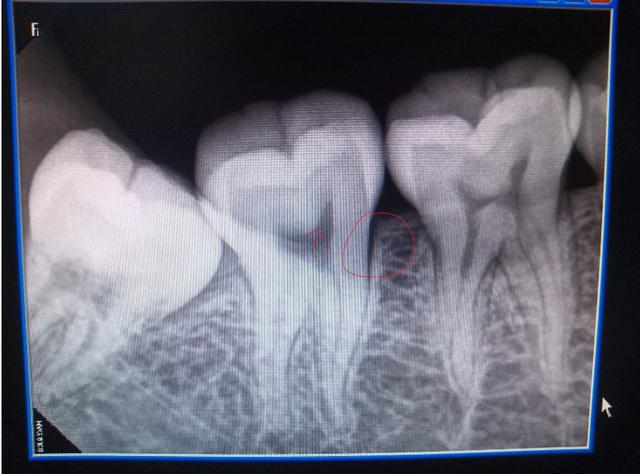

牙医还可能需要进行X射线检查,以检查智齿的排列并排除引起疼痛的其他可能原因,例如蛀牙。